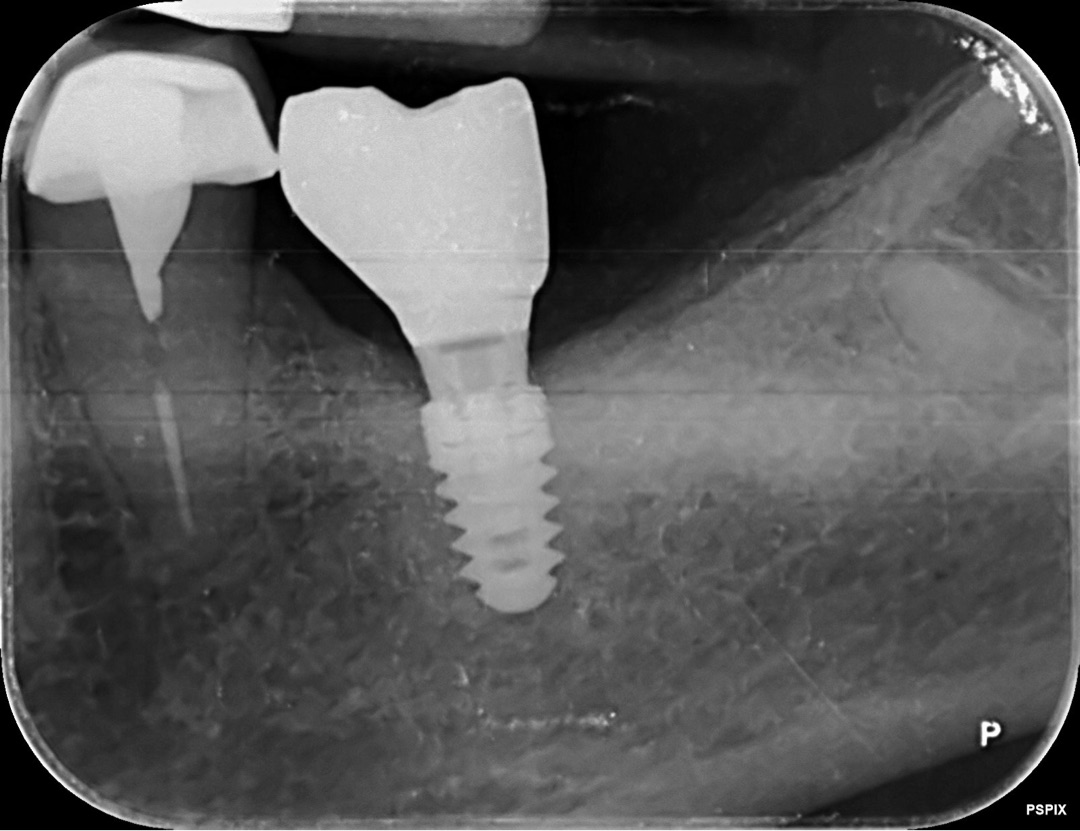

- Bone Level: el implante se coloca a nivel del hueso, la parte rugosa está en contacto directo con el hueso y luego usamos piezas intermedias (pilares) para salir a la encía, según explica Swiss Dental Solutions.

- Tissue Level: el implante tiene un “cuello” pulido que atraviesa la encía y la parte rugosa queda más protegida, como describe el Dr. Nikos Mattheos.

Los Bone Level dan mucha libertad protésica y estética, pero exigen una precisión enorme al trabajar, porque si no, aumentan los riesgos de problemas en los tejidos que rodean al implante.

Los Tissue Level, bien indicados, facilitan el mantenimiento de la salud de la encía alrededor del implante y simplifican un poco la biología de esa zona.

En mi práctica, uso implantes a nivel tisular (Tissue Level) en muchos casos porque me ayudan a proteger mejor los tejidos y a controlar de forma más predecible la zona crítica alrededor del implante.